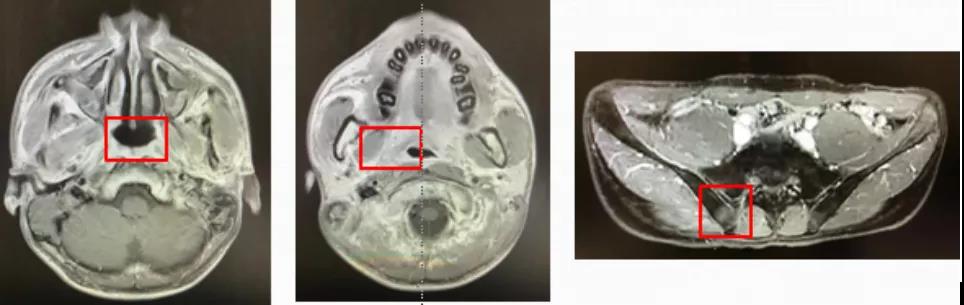

影像学评价:鼻咽、骨盆MR(2020年9月24日):可见鼻咽顶后壁黏膜增厚,范围约4mm×4mm;右侧颈部II-IV区多发转移淋巴结,大者直径约5mm,病灶较前变化不大。右髂骨转移瘤,直径约20mm,范围较前变化不大,强化较前减低;治疗前后MR变化见图3,从左至右依次为鼻咽部、右侧颈部淋巴结及右髂骨病灶。